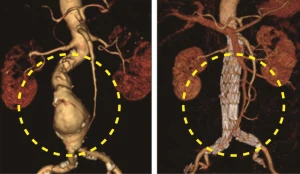

스텐트 삽입술

대동맥 내부에 혈관 내 이식편을 넣어 동맥류를 차단하고 혈액이 흐르는 새로운 통로를 만들어 줍니다.

대동맥 치환 수술

수술은 늘어난 대동맥을 제거하고 인조혈관을 치환하는 수술을 합니다